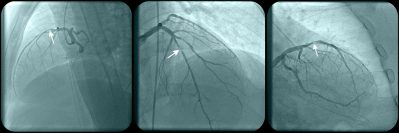

FAVOR III Europe was designed to test QFR against the FFR gold standard, looking not at concordance of result but rather at clinical outcomes. To this end, 2,000 patients were enrolled at 34 centers in 11 European countries. After stratification by diabetes status and presence or absence of disease in the left anterior descending artery, subjects were randomly assigned to either an FFR- or QFR-based treatment strategy.

For both FFR and QFR, a value of ≤ 0.80 was used as the cutoff for proceeding to revascularization. The average QFR value was 0.84, compared with an average of 0.81 for FFR. In the QFR group, 46.2% of lesions were identified as significant compared with 38.2% of lesions in the FFR group. This resulted in 27% higher stent use in the QFR group: 823 in the QFR group and 650 in the FFR group. Lesions in the circumflex distribution specifically were more than twice as likely to be functionally significant by QFR compared with FFR.